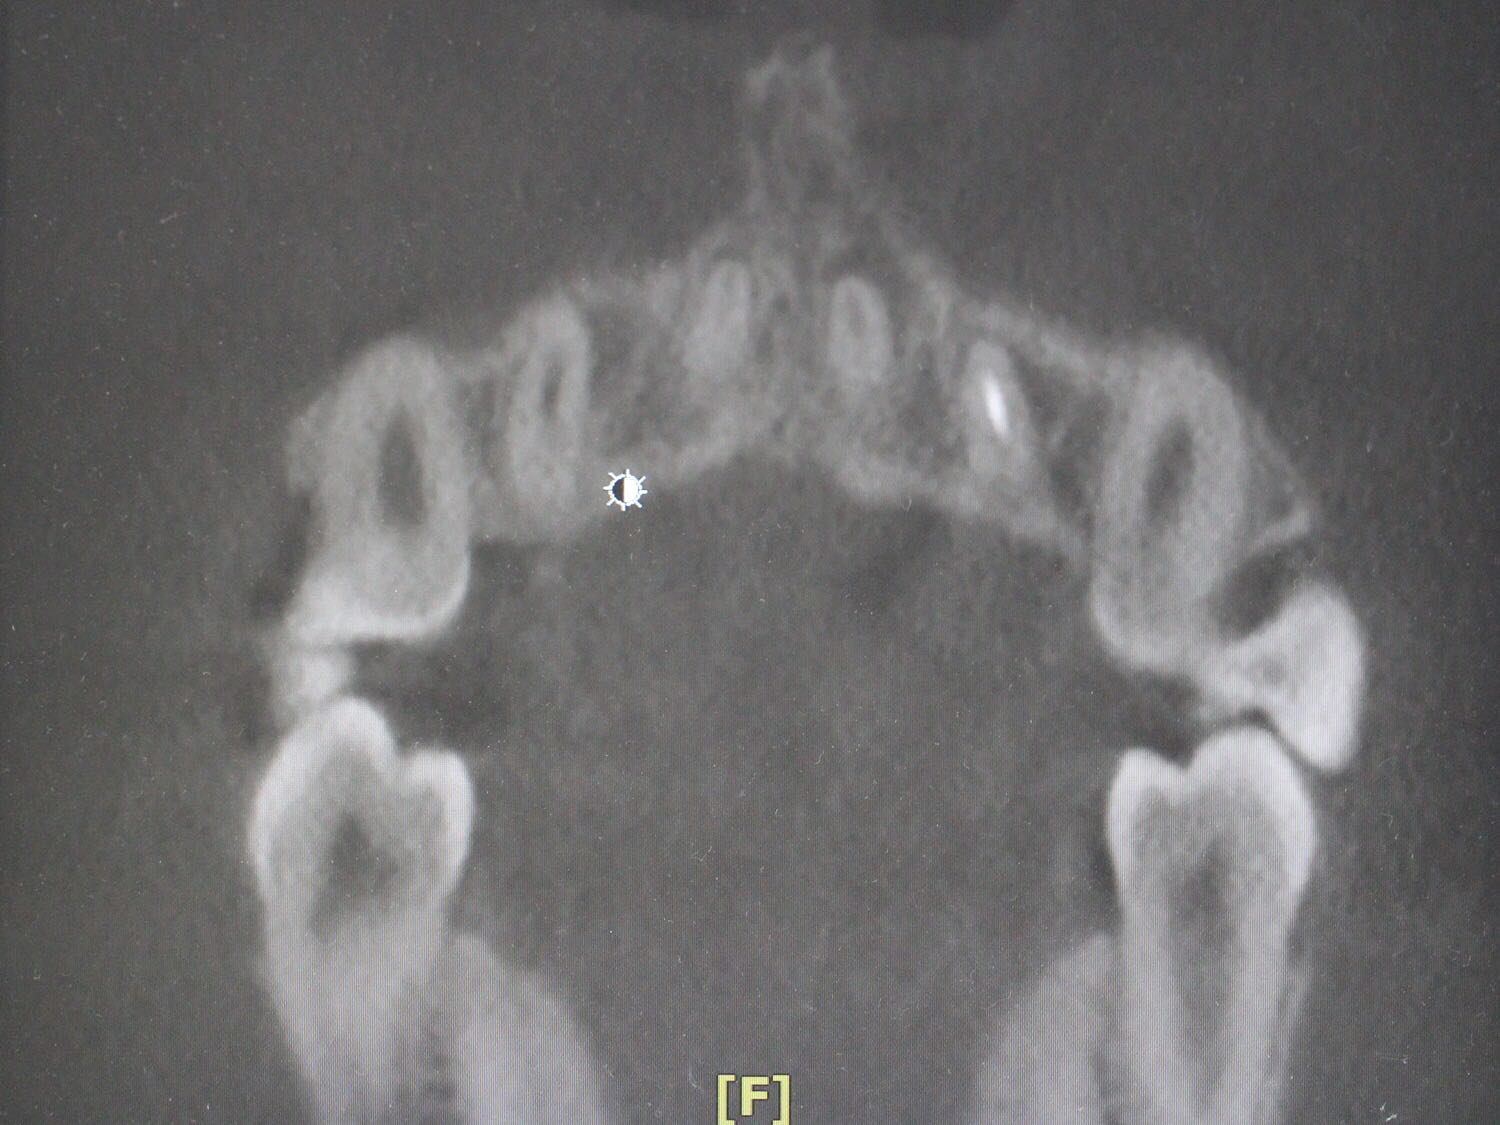

检查:12牙未见明显龋坏,探(-),冷(-),叩(++),无明显松动,牙髓电活力测试无反应,唇侧牙槽粘膜处未见窦道。 X线片:12牙根尖周暗影?

诊断:12牙牙髓坏死? 治疗方案: 1、12牙根管治疗+充填治疗+冠修复 2、12牙择期治疗 3、12牙显微根尖外科手术 4、12牙拔除 5、12牙观察 治疗计划:与患者交流沟通并详细介绍每种治疗方案、费用、时间、预后等,由于患牙根尖病变范围较大,预后欠佳。患者知情、同意并选择方案2,签署知情同意书。 12牙涡轮机开髓,探查根管口,10#,15#K锉疏通根管,根长测量仪测量根管长度,12牙22.5mm,髓腔和根管内放置根管润滑剂,S3扩锉至2506,拍片试尖,X线片示主尖合适。次氯酸啊冲洗根管,P5荡洗,纸尖干燥根管,置氢氧化钙,Caviton暂封。

处置:12牙去暂封,去棉球,根管及髓腔消毒并再次测量并确定根管长度,干燥后,显微镜下使用根尖孔生物材料加大锥度牙胶尖及热牙胶行根尖屏障封闭成形及根管充填,再拍X线片检查根充效果,X线片示根充良好,窝洞消毒,暂封。 医嘱:不适随诊,勿用患牙进食

侧切牙是畸形舌侧沟的好发牙位 釉质发生卷曲 一定程度后 可以形成牙中牙 该部位容易形成细菌通道造成根周的感染 治疗效果欠佳 在完善根管治疗后 应长期随访 必要时行外科手术 如果仍不能有效控制感染 则考虑拔牙